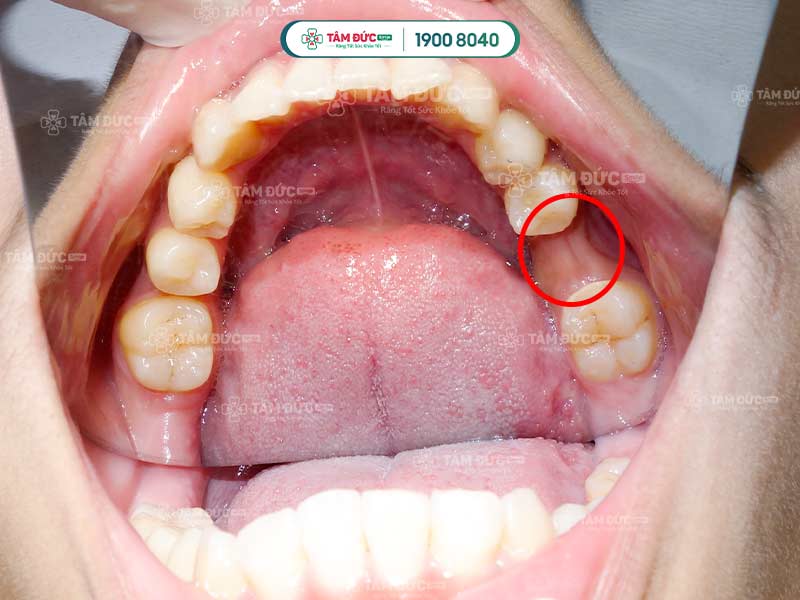

Tụt lợi hở chân răng còn được gọi là teo lợi. Đây là hiện tượng chân răng bị lộ ra do mô nướu co lại hoặc di chuyển mạnh mẽ.

Thống kê cho thấy, tình trạng này thường xuất hiện ở các răng phía ngoài như răng nanh, răng cửa.

Ở giai đoạn đầu, tụt lợi hở chân răng phát triển một cách âm thầm nên rất khó nhận biết. Quý khách chỉ nhận ra khi mô nướu đã bị teo và phần chân răng lộ nhiều hơn. Lúc này, Quý khách có thể cảm thấy ê buốt, đau nhức và dễ bị chảy máu chân răng.

2.5. Tiêu xương ổ răng làm tụt lợi hở chân răng

Khi xương ổ răng bị mất dần do các yếu tố như di truyền, suy dinh dưỡng, thì phần chân răng sẽ bị lộ ra ngoài. Lớp nướu không còn được nâng đỡ dần trở nên lỏng lẻo và bị kéo tụt xuống.

Tiêu xương ổ răng càng nghiêm trọng càng đẩy nhanh tiến độ bị tụt lợi hở chân răng. Việc bổ sung đầy đủ dinh dưỡng và phòng ngừa tiêu xương răng là rất cần thiết để ngăn ngừa tụt lợi.